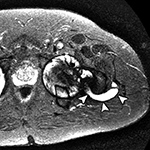

Adverse reaction to metal debris with posterior pseudotumor. Axial T1-weighted fast spin echo (FSE) (A) and STIR (B) MR images demonstrate left peritrochanteric fluid collection (arrow in A and arrowheads in B) arising from the left hip joint in a patient with metal-on-metal hip arthroplasty. Note the thin low T2 signal rim surrounding the fluid collection representing metal deposition. |